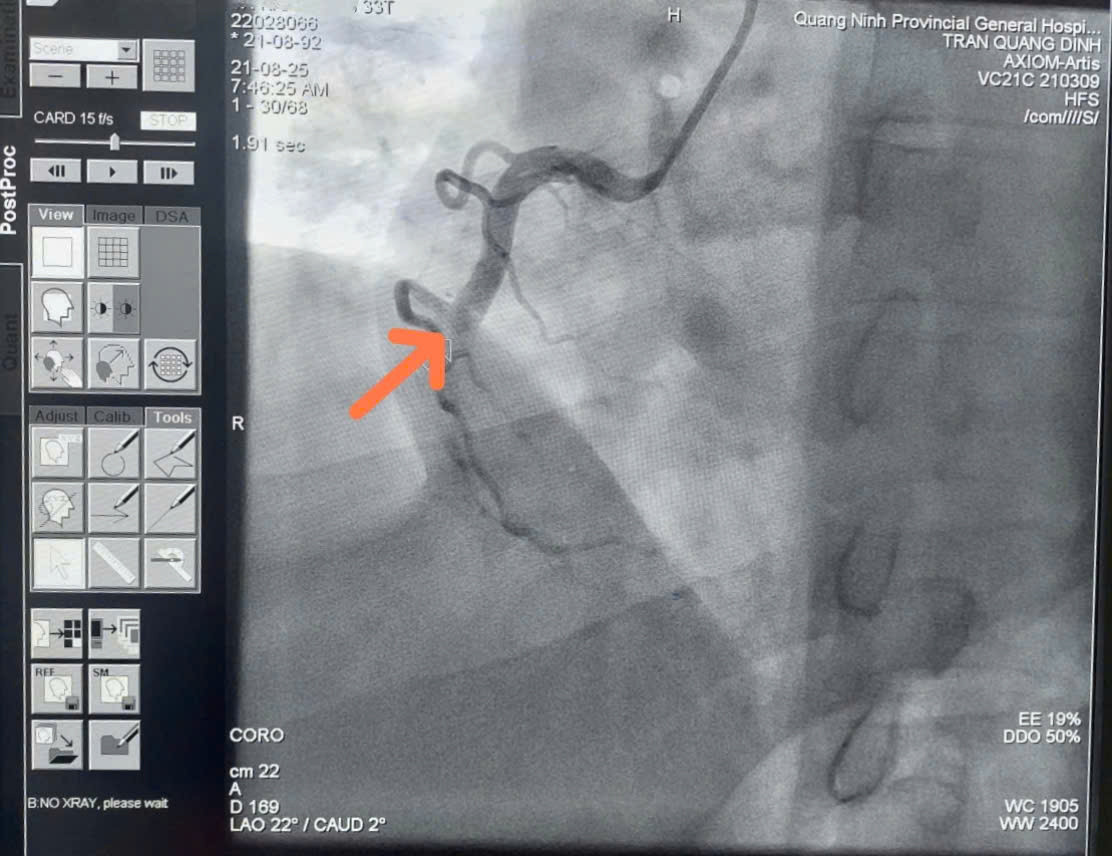

Một trường hợp khác như anh T.Q.K (33 tuổi, Cẩm Phả, Quảng Ninh), được đưa đến Bệnh viện Đa khoa khu vực Cẩm Phả vào sáng 21/8, trong tình trạng đau ngực dữ dội, khó thở khi đang làm việc. Trước đó, anh hoàn toàn khỏe mạnh, không có tiền sử bệnh lý. Tại bệnh viện, kết quả điện tâm đồ cho thấy anh bị nhồi máu cơ tim cấp thành dưới. Ngay lập tức, các bác sĩ hội chẩn trực tuyến với chuyên gia tim mạch từ Bệnh viện Đa khoa tỉnh Quảng Ninh và chuyển tuyến khẩn cấp.

Tại đây, chụp động mạch vành phát hiện anh K. bị tắc hoàn toàn đoạn 2 động mạch vành phải. Ê-kíp can thiệp kịp thời đặt stent, tái thông dòng chảy mạch vành, giúp anh may mắn thoát nguy kịch.